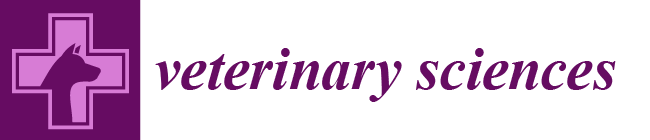

2.3. Diagnostic Imaging under Anesthesia

2.4. Surgical Treatment